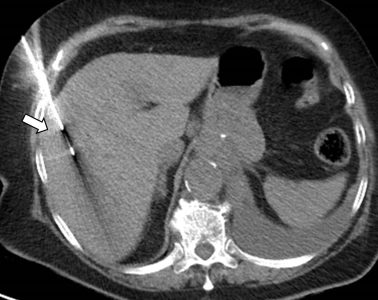

Ακτινολογία

Διαδερμικά κατευθυνόμενη βιοψία ήπατος σε μεταστατικό καρκίνωμα μαστού